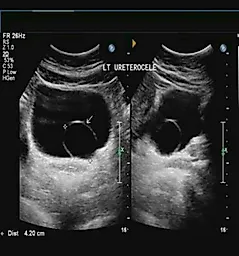

Описано применение ультразвукового метода обследования пациентов со стриктурами мочеиспускательного канала. Он, по некоторым данным, позволяет лучше определить глубину спонгиофиброза. Однако наше впечатление, основанное на клинической практике, свидетельствует о небольшой информативности ультразвукового исследования в дополнение к методам, описанным выше.